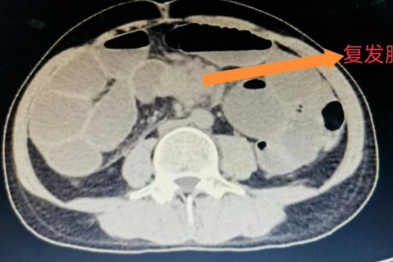

河北一洲肿瘤医院外科成功救治结肠癌复发合并完全性肠梗阻患者